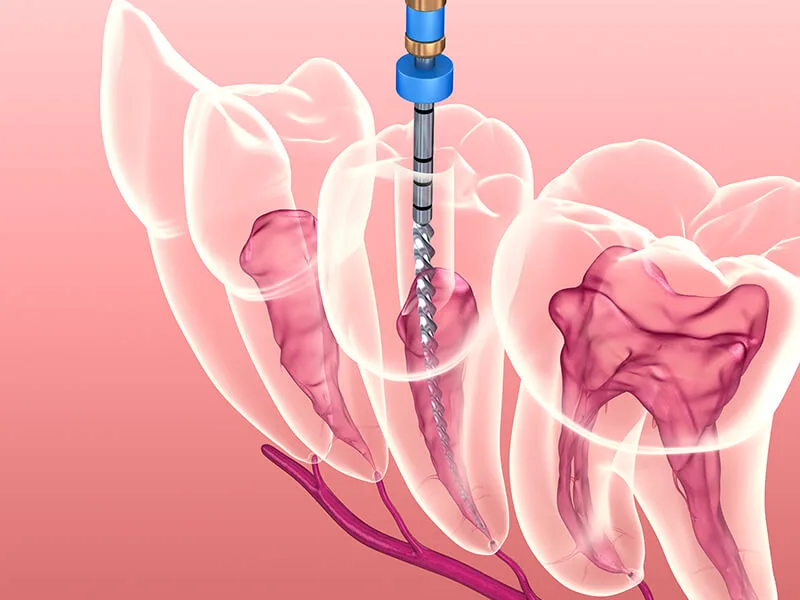

A endodontia é o tratamento odontológico especializado focado na remoção da polpa dentária infectada ou inflamada. Este procedimento é essencial para a saúde bucal, pois promove a desinfecção profunda dos canais radiculares no cotidiano.

A tecnologia moderna permite que a endodontia seja realizada de forma rápida e precisa. O uso de microscopia e localizadores apicais torna as etapas do processo nítidamente mais confortáveis e seguras para o paciente.

O fluxo do tratamento envolve etapas coordenadas para assegurar a limpeza completa do canal. O dentista realiza avaliações clínicas e radiográficas detalhadas antes de iniciar a desinfecção e o selamento dos canais.